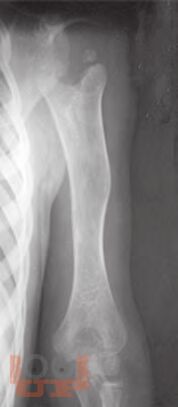

Ортопедические последствия гематогенного остеомиелита верхних конечностей у детей

Авторами представлен многолетний опыт лечения детей с ортопедическими последствиями гематогенного остеомиелита верхних конечностей. На основании комплексного обследования пациентов предложены оптимальные способы лечения детей с данной патологией.

Издание предназначено для травматологов-ортопедов и хирургов широкого профиля.